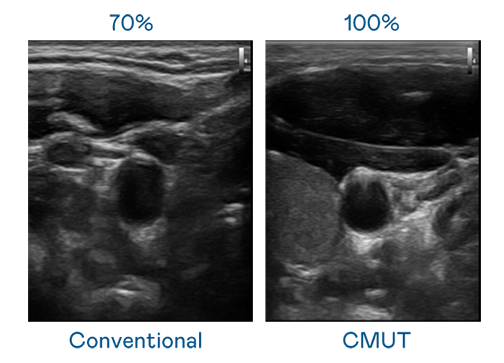

CMUT 技术是一种用电容式微机电元件来产生超音波讯号的技术。与传统 PZT 压电式技术相比,CMUT 频宽增加 30%,更宽频的超音波讯号让影像解析度大幅提升,是实现高影像品质医疗超音波扫描、促进精准医疗发展的关键技术。

超音波影像的解析度高低,首先取决于探头能发出的讯号频宽。果冻天美乌鸦星空 CMUT 可提供高清晰的超音波讯号,提供高频宽、高灵敏度、影像纹理细节更高的超音波影像,协助医护人员缩短影像判读时间及利用精准的医疗影像进行诊断。